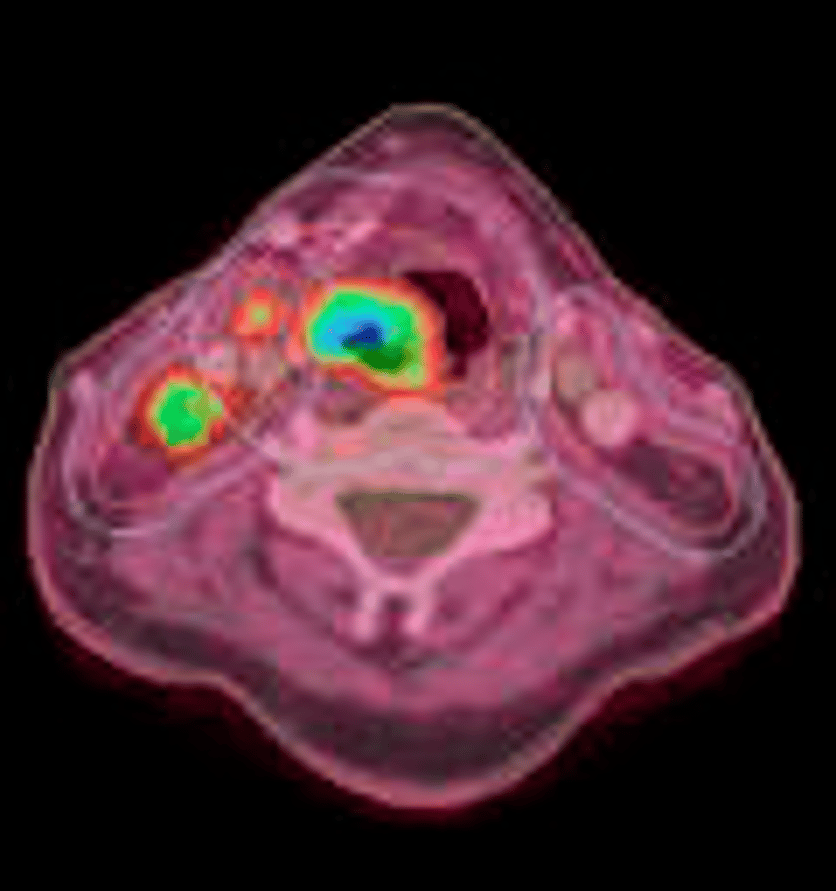

Bilden ovan visar en halstumör (det stora blågröna området i mitten) och två lymfkörtelmetastaser. Tack vare PET får man även biologisk information vilket är viktigt både vid diagnostik och dosplanering.